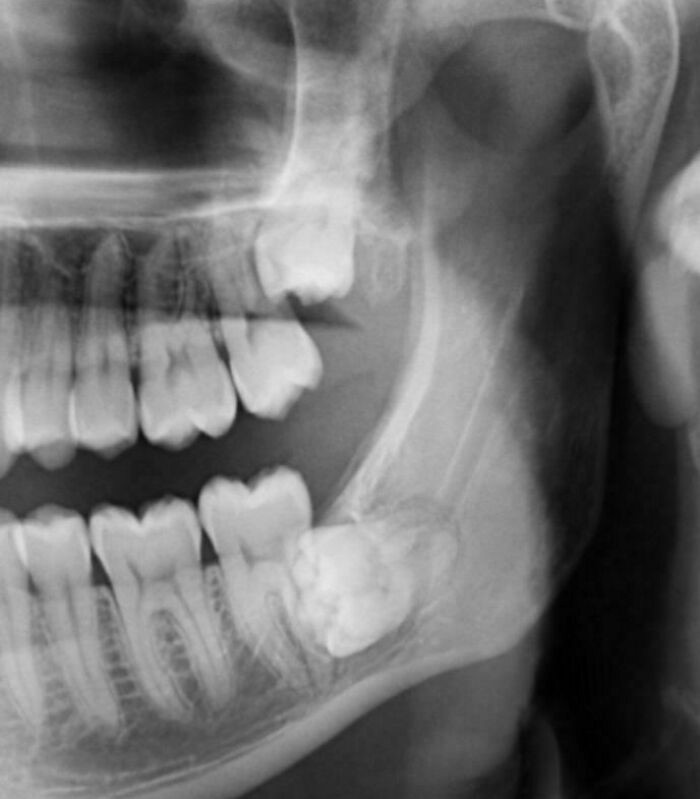

Kondisi Tubuh Manusia Ini Bikin Takjub dan Merinding